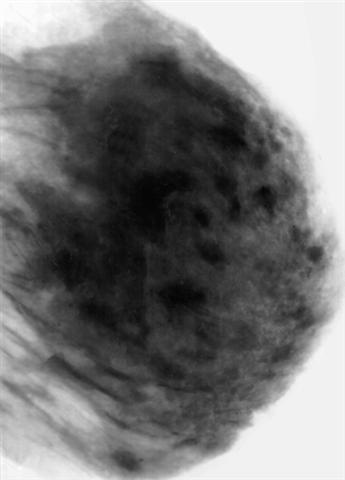

Рис. а). Маммограмма в норме.